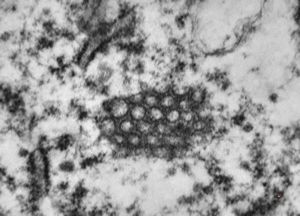

M,26y. | ribosome-lamella bodies in adenocarcinoma

M,41y. | ribosome-lamella complex in tricholeukocyte -hairy cell leukemia, spleen

M,41y. | ribosome-lamella complex in tricholeukocyte -hairy cell leukemia, spleen

M,41y. | ribosome-lamella complex in tricholeukocyte -hairy cell leukemia, spleen